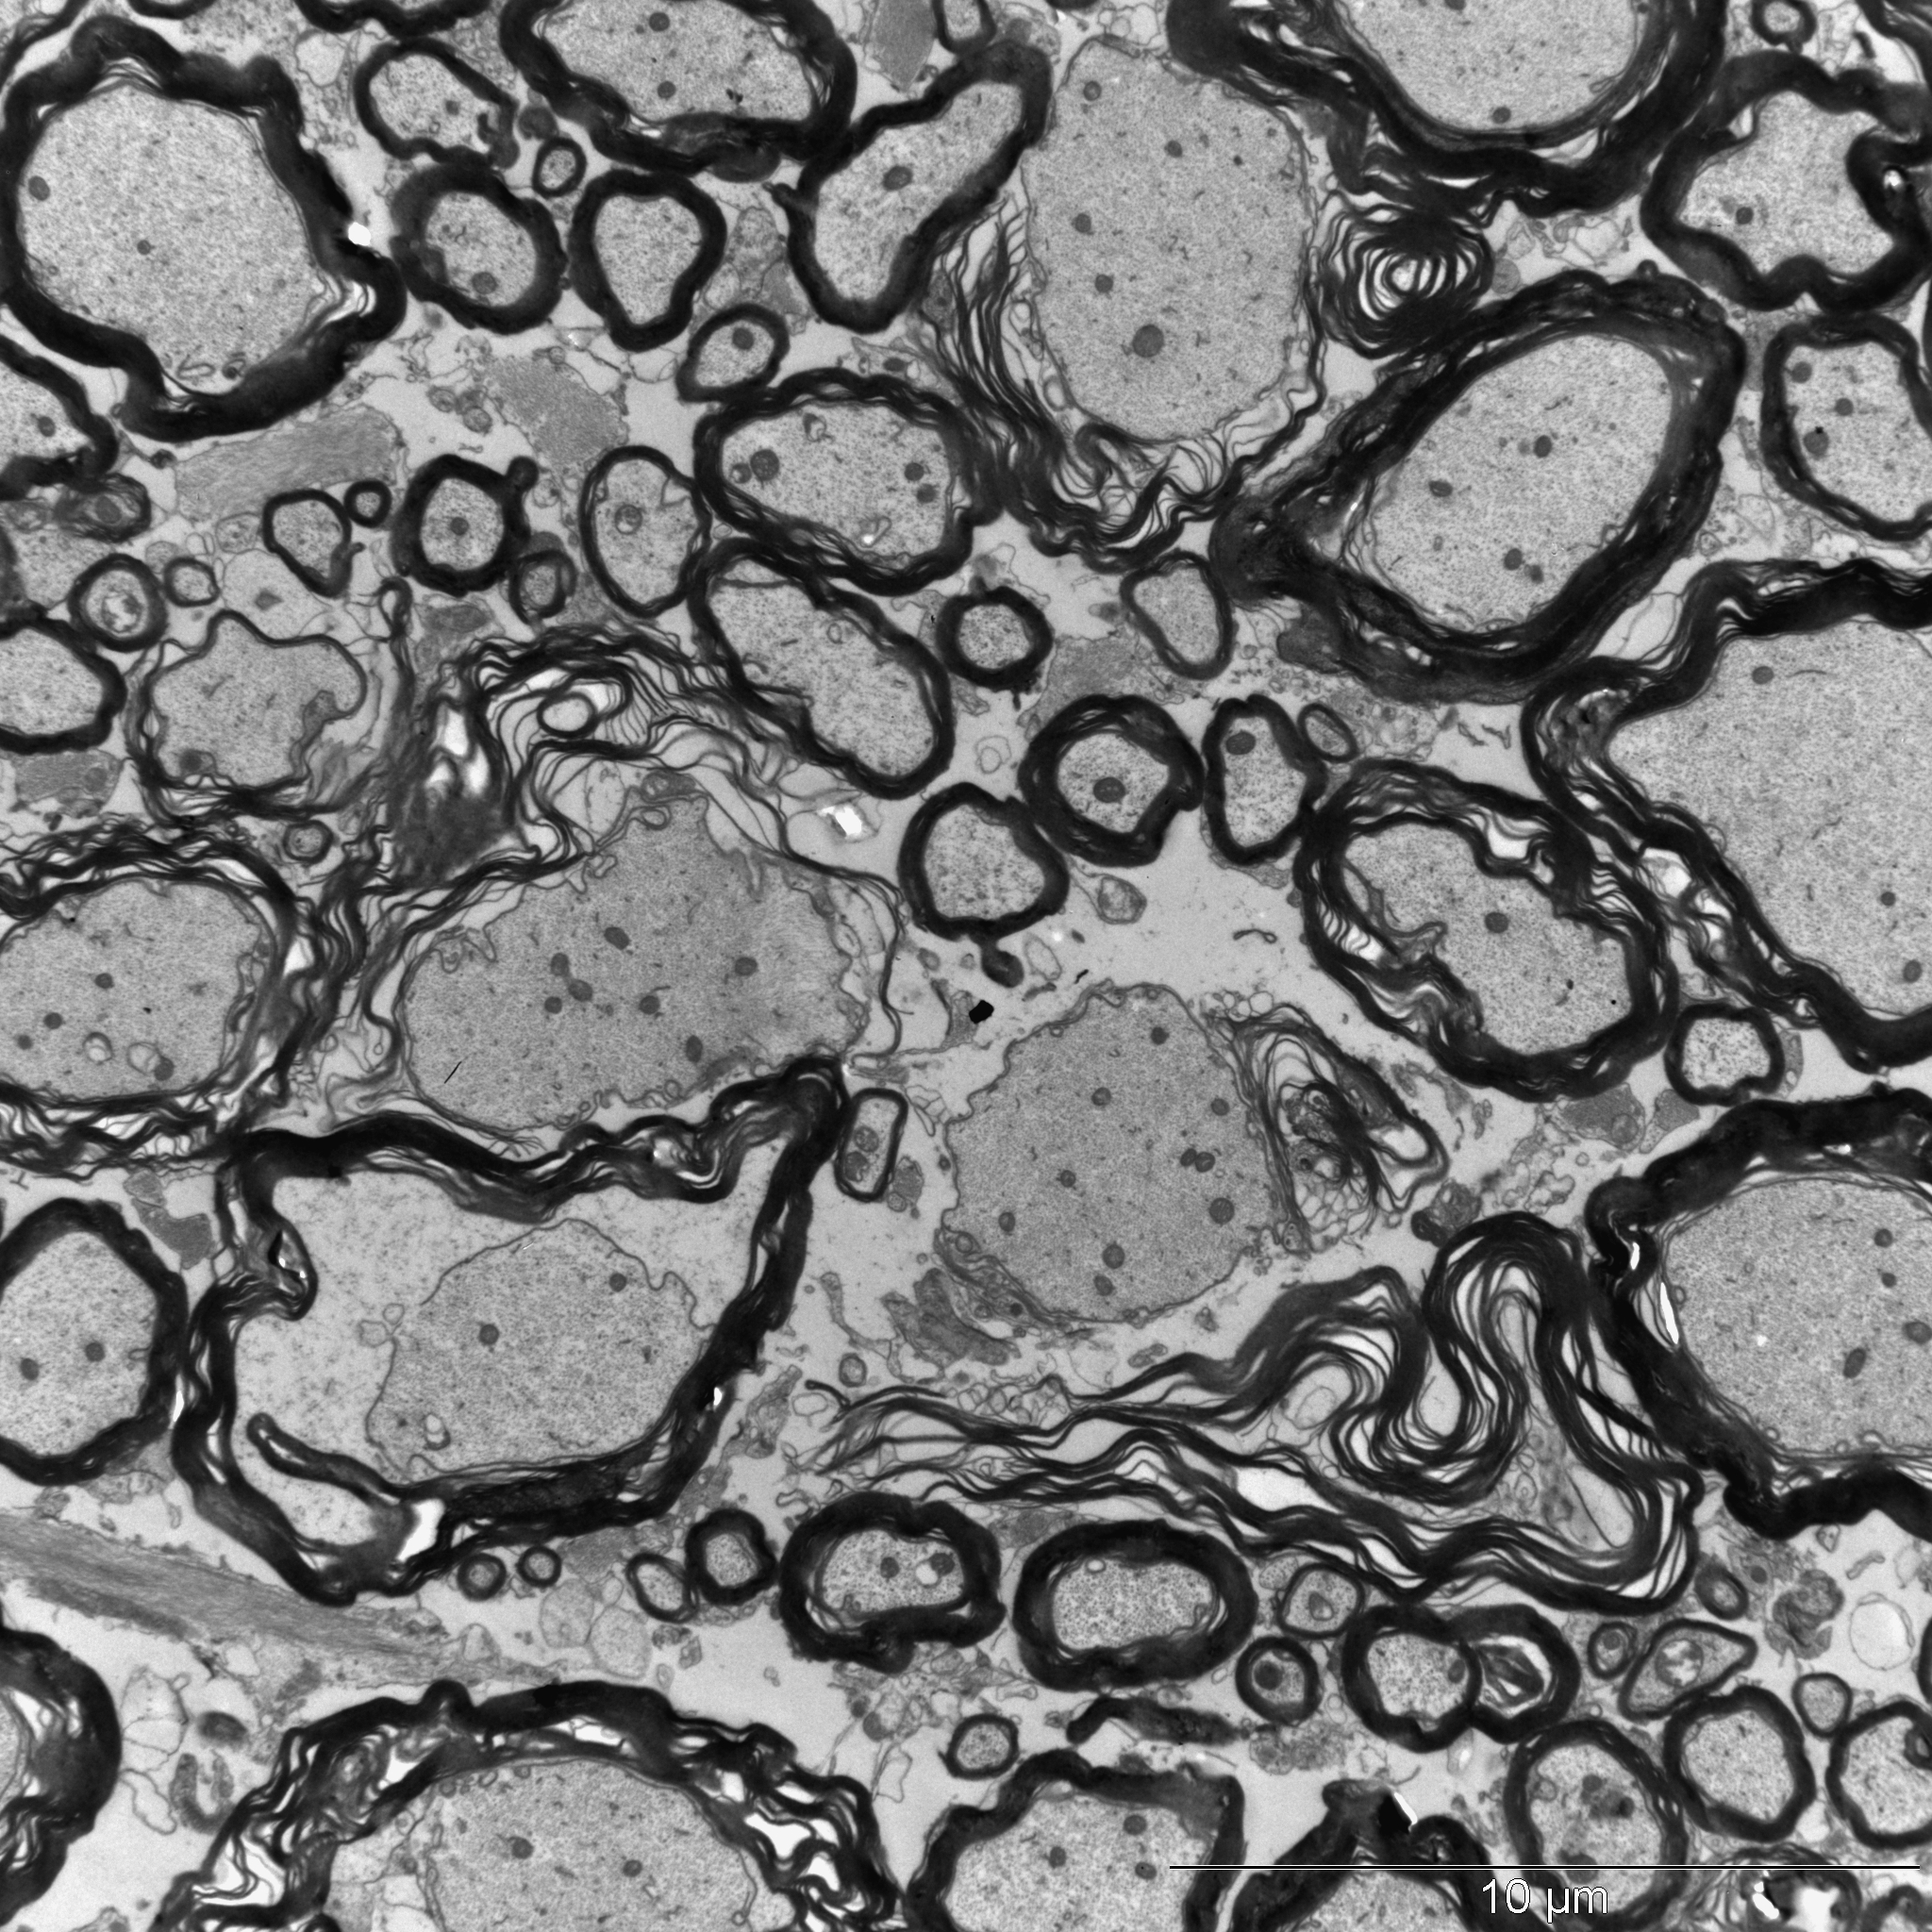

Tatsächlich wurden die Forschenden fündig: Wenn sie den Tieren den Kuhmilch-Inhaltsstoff Casein zusammen mit einem Wirkverstärker verabreichten, entwickelten die Mäuse danach neurologische Störungen. Unter dem Elektronenmikroskop zeigte sich, dass bei ihnen die Isolierschicht um die Nervenfasern geschädigt war, das Myelin. Die fettähnliche Substanz verhindert Kurzschlüsse und beschleunigt zusätzlich erheblich die Reiz-Weiterleitung.

Durchlöcherte Myelinschicht

Bei Multipler Sklerose zerstört das körpereigene Immunsystem die Myelin-Ummantelung. Die Folgen reichen von Missempfindungen über Probleme beim Sehen bis hin zu Bewegungs-Störungen. Im Extremfall enden die Betroffenen im Rollstuhl. Auch in den Mäusen war die isolierende Hülle massiv durchlöchert - offensichtlich ausgelöst durch die Casein-Gabe. „Als Grund vermuteten wir ähnlich wie in MS-Kranken eine fehlgeleitete Immunreaktion“, erklärt Rittika Chunder, die in der Arbeitsgruppe von Prof. Kürten habilitiert. „Die körpereigene Abwehr attackiert eigentlich das Casein, zerstört dabei aber auch Proteine, die an der Bildung des Myelins beteiligt sind.“

In den Casein-behandelten Mäusen richtete sich die körpereigene Abwehr also auch gegen MAG, wodurch das Myelin destabilisiert wird. Doch inwieweit lassen sich die Ergebnisse auf Menschen mit MS übertragen? Um diese Frage zu beantworten, gaben die Forschenden Casein-Antikörper von Mäusen zu menschlichem Hirngewebe. Tatsächlich reicherten sie sich dort an den Zellen an, die im Gehirn für die Myelin-Produktion verantwortlich sind.